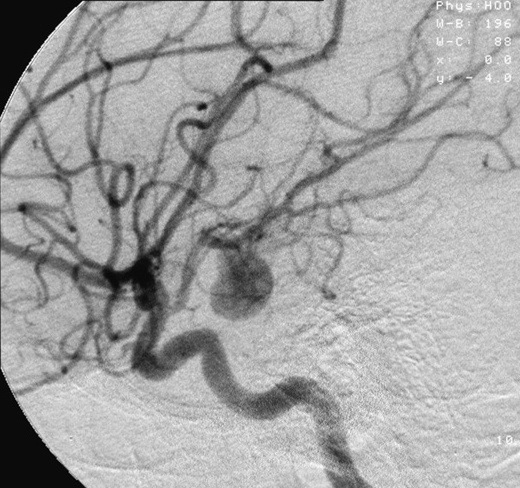

What is an aneurysm?

A brain aneurysm, or cerebral aneurysm, is a bubble on the surface of the artery in the brain. Aneurysms can occur anywhere in the body, but when talking about stroke, these are aneurysms of the brain.

Roughly two-percent (2%) of the world’s population has an unruptured brain aneurysm, according to the Brain Aneurysm Foundation. However, these are typically non-life-threatening as long as they remain small and do not cause pressure. Unruptured brain aneurysms do not always cause symptoms and are typically discovered accidentally for another procedure.

However, if the brain aneurysm bursts, this is a life-threatening medical emergency condition called a subarachnoid hemorrhage. A subarachnoid hemorrhage is a ruptured brain aneurysm that causes blood to pool into the space around the brain creating pressure. A subarachnoid hemorrhage can lead to permanent brain damage or death. The main symptom of a subarachnoid hemorrhage is a sudden headache.

What is the treatment for an aneurysm?

Most brain aneurysms are treated by endovascular thrombectomy. A catheter the size of an iPhone charging cable is inserted into the artery of the leg or arm, through which a series of smaller catheters between 0.035 inches and 0.074 inches are inserted through navigate all the way up to the brain to plug the aneurysm and prevent rupture or re-rupture.

Using this technique, an endovascular thrombectomy allows navigation all the way up into the brain to pull out blood clots of large vessel occlusion. In the case of aneurysms, which are a bubble on the surface of an artery, we can navigate a small catheter into that aneurysm and actually fill the aneurysm, plug it up, and prevent it from re-rupturing.